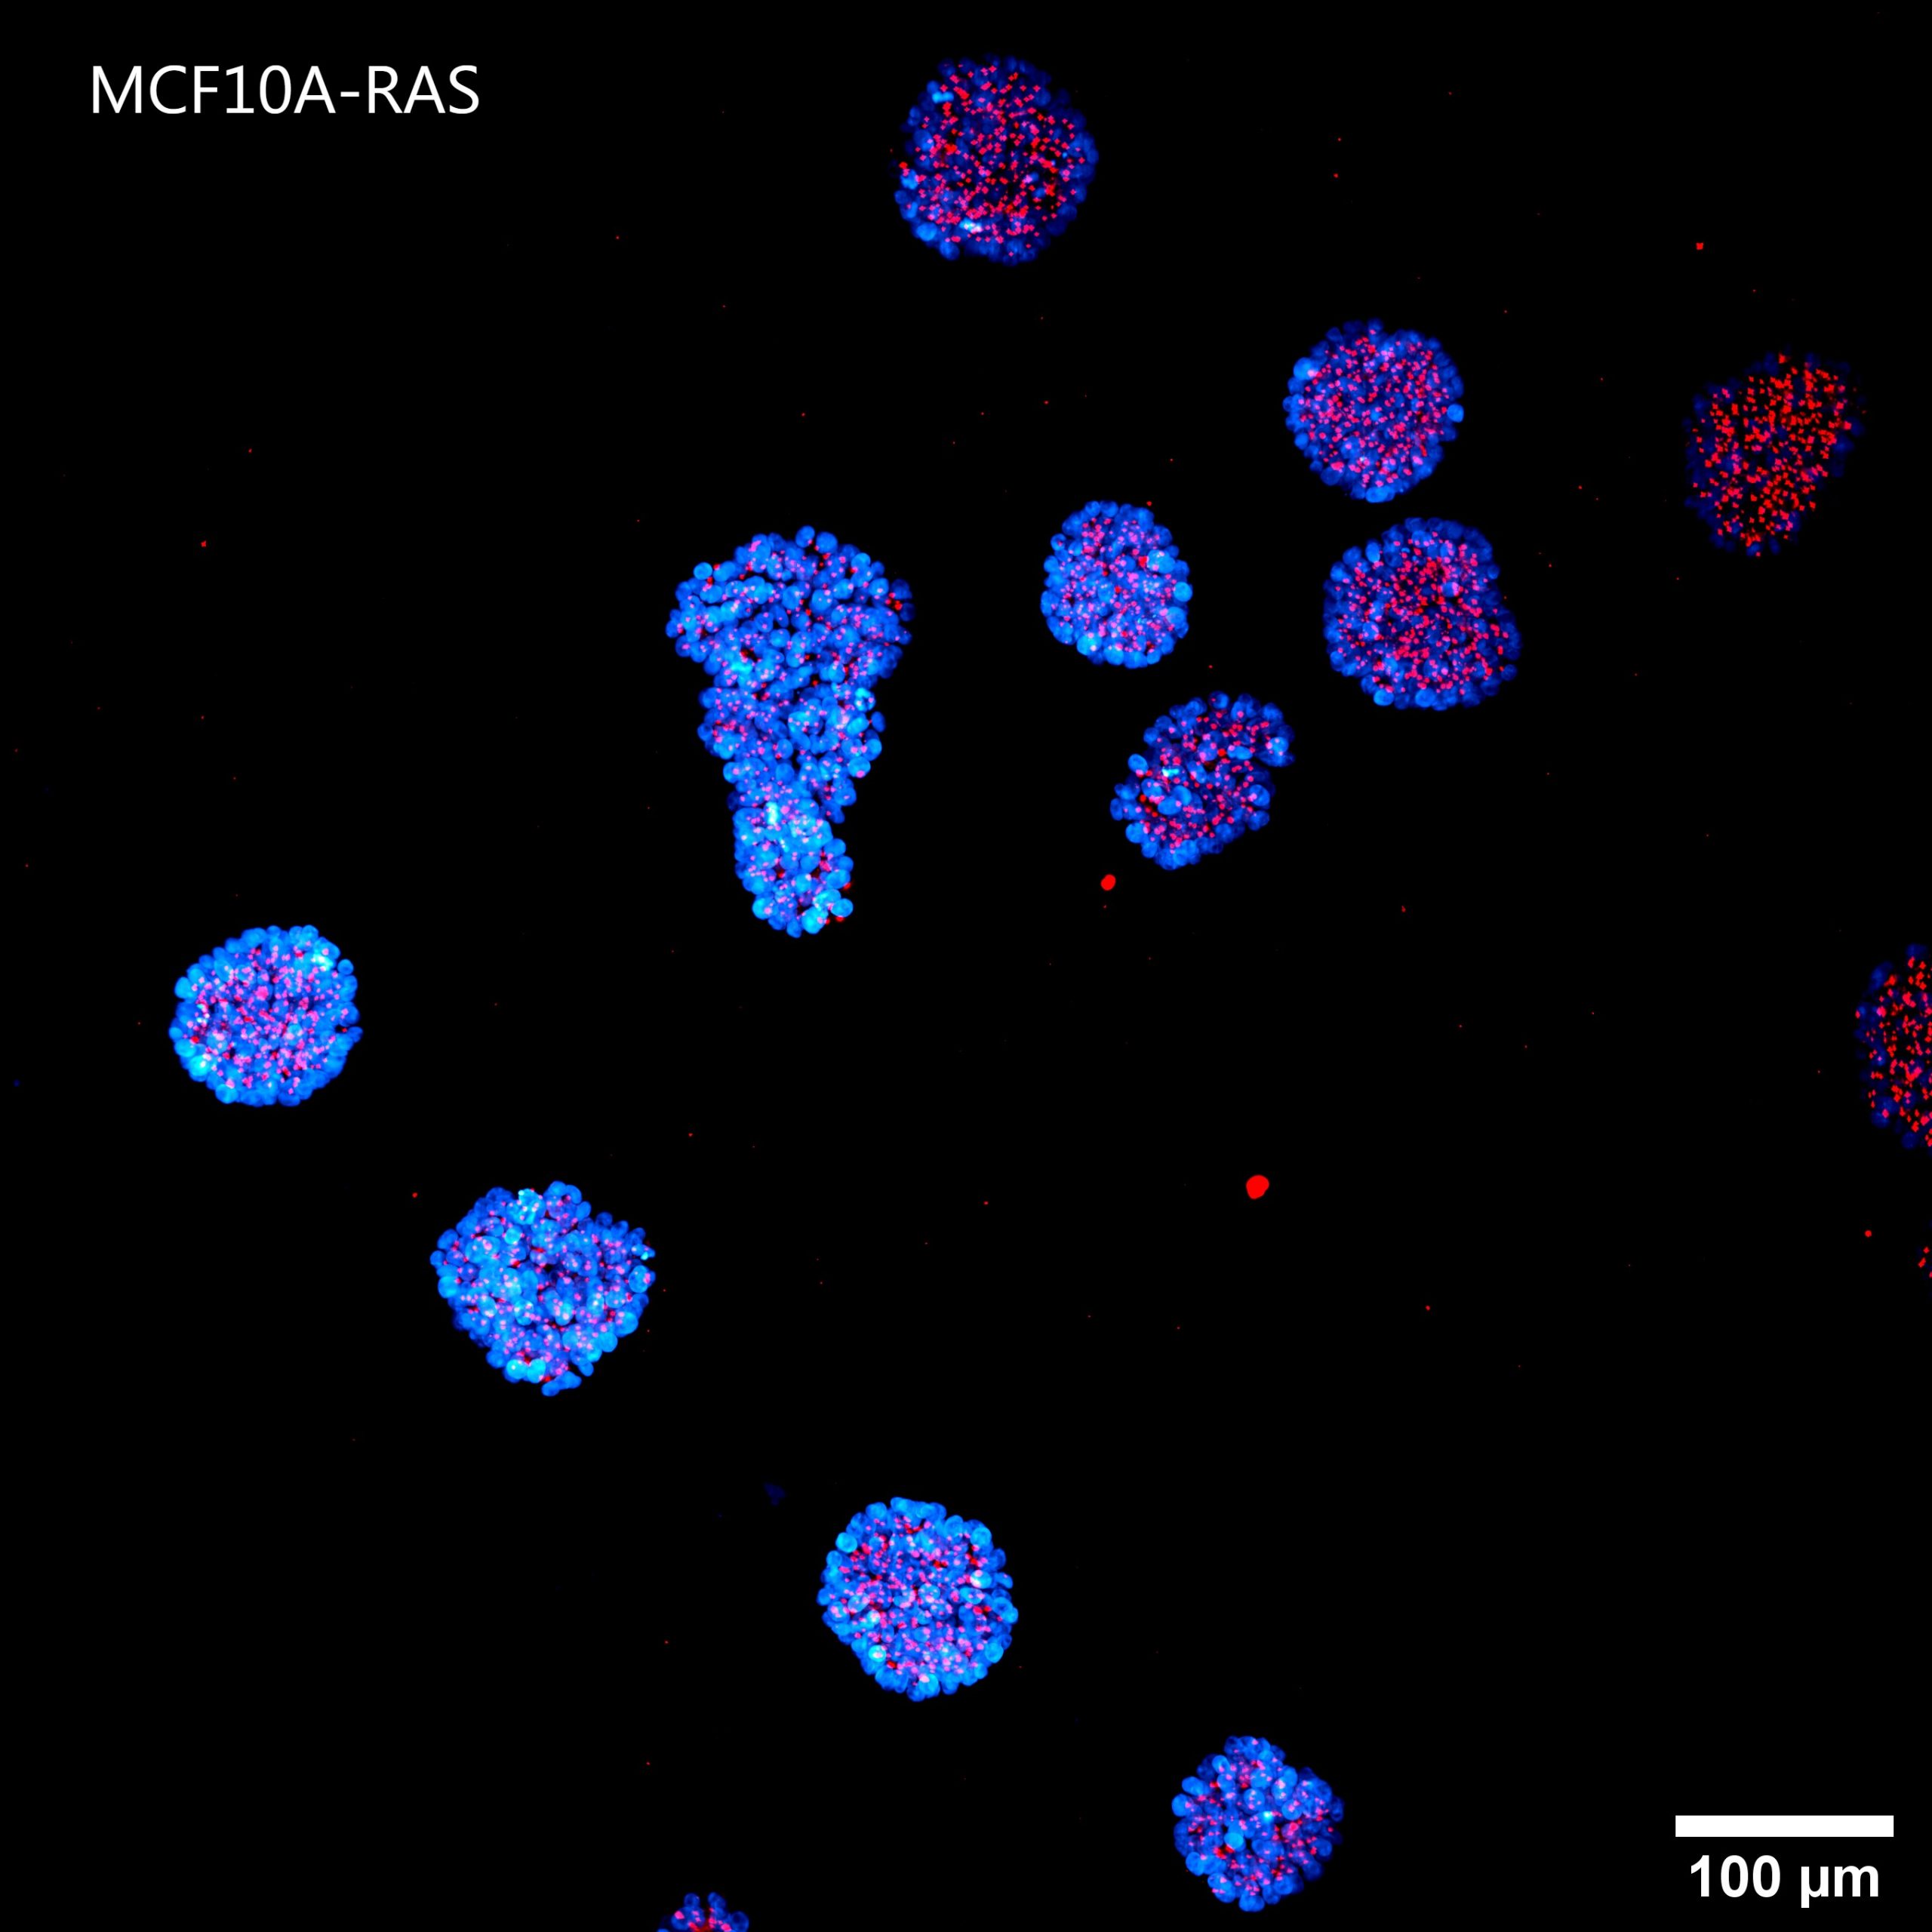

Figure 4 shows a maximum intensity projection (MIP) of 60 um Z-stack of non-malignant (A) and tumorigenic (B) acini. By providing homogeneous illumination over the entire 25 mm field of view (FOV), the X-Light V3 confocal spinning disk allowed us to analyze a large number of acini, reducing the number of images required to obtain robust data and, therefore, minimizing acquisition time.

B

Figure 4: MIP from 60 um Z-stack of non-malignant (A) and tumorigenic acini (B). Cells were cultured in 3D Matrigel suspensions and stained with pericentrin (red) and DAPI (blue). These images were acquired with a CFI Plan Apochromat Lambda D 20x air objective (20x, Nikon, 0.8 NA and 0.8 mm WD).

Using such an automated analysis pipeline, we have collected a wide range of information useful in understanding how mutated Ras receptors affect the proliferation and morphology of acini. As shown in Figure 8A, acinar structures from cultures of non-malignant breast cancer typically have round symmetrical shapes. On the other hand, the acini from malignant breast cancer cultures cause a deformation in the 3D architecture which causes the shape of the acini to be more elongated and deconstructed. Notably, the spheroids derived from the MCF10A K-Ras engineered line has a significant volume increase compared to the control line (Figure 8B). In fact, the transforming contribution of the k-Ras oncogene correlates with the increase in the cellular proliferative rate, and this causes an increase in volume already after 6 days in culture.

A

Figure 8: Representative MCF10A-CTR and MCF10A-RAS acini (A) and volume analysis (um3) (B). Cells were cultured in 3D Matrigel suspensions and stained with pericentrin (red) and DAPI (blue). This image was acquired with a CFI Plan Apochromat Lambda D 20x air objective (20x, Nikon, 0.8 NA and 0.8 mm WD). Volume comparison between MCF10A-CTR and MCF10A-RAS acini (B).